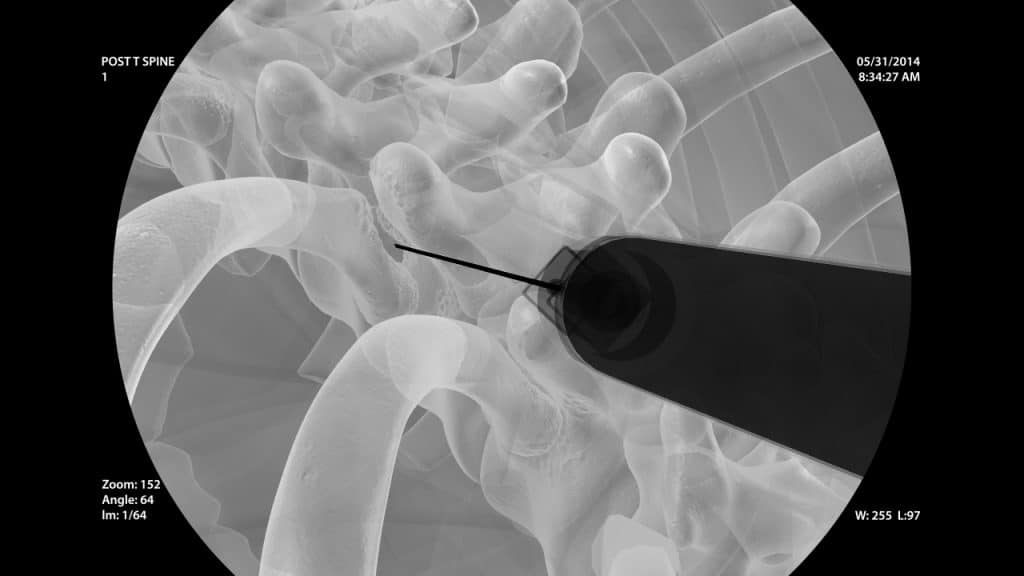

Die oben genannte Erkrankung kann durch Ausschaltung der Nozizeptoren (Schmerzrezeptoren) in den Kostotransversalgelenkkapseln durch vorübergehende Blockade mit einem Lokalanästhetikum behandelt werden. Zudem kann, wenn nötig, die Kombination eines Lokalanästhetikums mit einem Kortikosteroid eingesetzt werden. Diese bestimmte Technik wird üblicherweise unter Bildwandlerkontrolle durchgeführt.